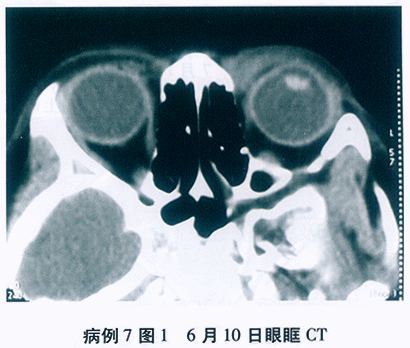

(2)眼部B超检查

首诊B超(见图37-5)结论: 右眼玻璃体前中段中-大量点状回声,颞下球壁前波浪样带状强回声, 距离球壁3~4,脉脱1~6mm, 左眼前中段少-中量点状回声,双眼后极球壁前带状回声, 双眼玻璃体混浊伴后脱离可能,后极网膜水肿可能, 右眼玻璃体混浊伴网脱脉脱可能。